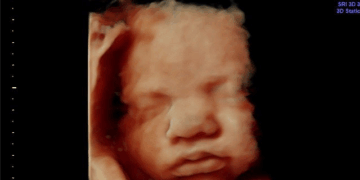

President Donald Trump on Wednesday nominated Dr. Nicole Saphier, a board-certified radiologist and dedicated pro-life advocate as his choice for Surgeon General. Saphier has been praised for her decision to choose life for her unborn child…